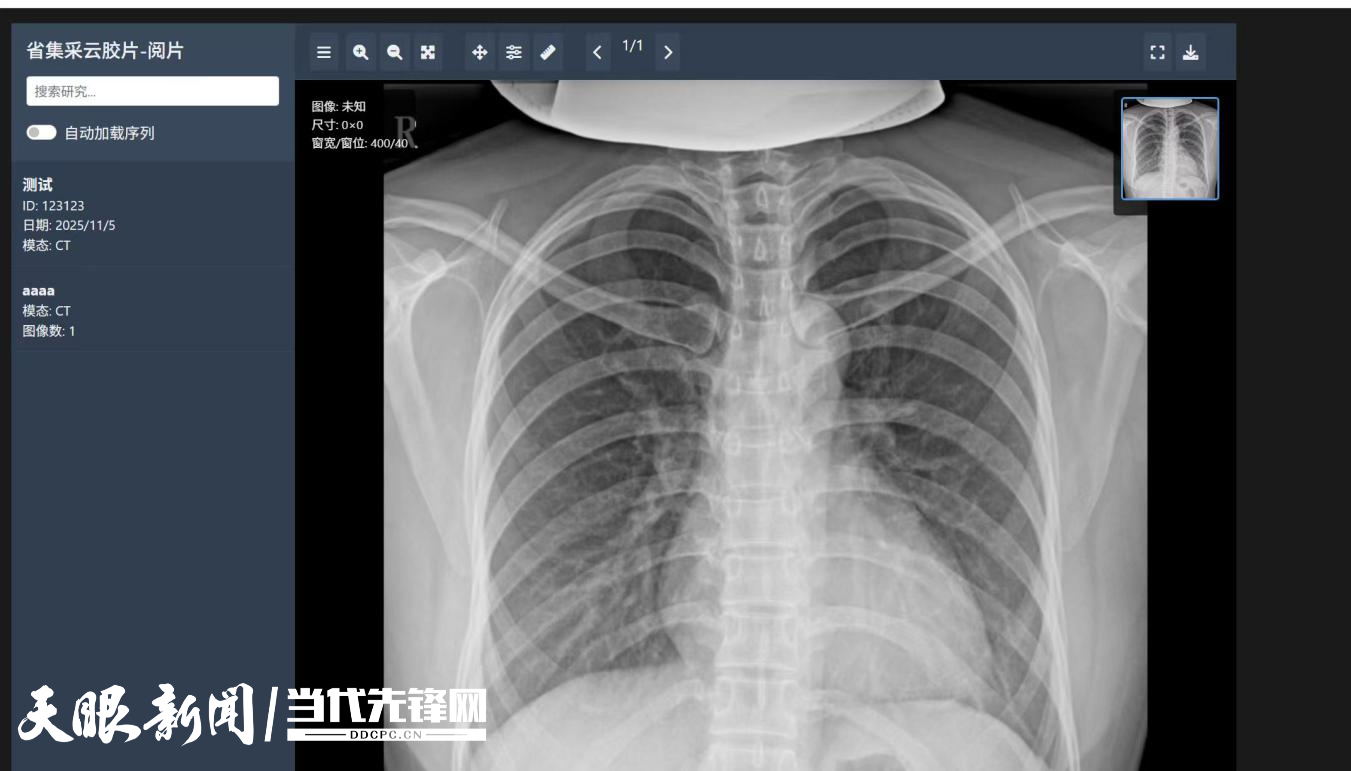

10月30日,六盘水市钟山区人民医院率先与医保影像(贵州)中心对接,成功实现患者全序列原始影像、诊断报告及个人信息数据上传,成为全国首家按照“集采+运营”模式落地云胶片上传的医疗机构,这标志着贵州省医保影像云互联互通建设取得实质性突破,也为区域内医疗机构提供了可复制、可推广的成功经验。

按照《国家医疗保障局 贵州省人民政府数据赋能医保高质量发展先行区合作共建协议》,建设省级集中统一的医保影像云中心,探索推进医疗影像数据的省级归集、诊疗行为真实核验、医保数据赋能应用、跨区域调阅共享及人工智能深度应用,实现患者就医更便捷、医院管理更高效、基金运行更安全、区域医疗更协同的多赢局面,是推动医保服务高质量发展的重要引擎。

截至11月6日,贵州省人民医院、贵州医科大学附属医院、北京积水潭贵州医院、玉屏县人民医院等医疗机构陆续实现数据上传,其他医疗机构也在积极推进影像云专网环境部署、前置机调试及系统接口改造工作。